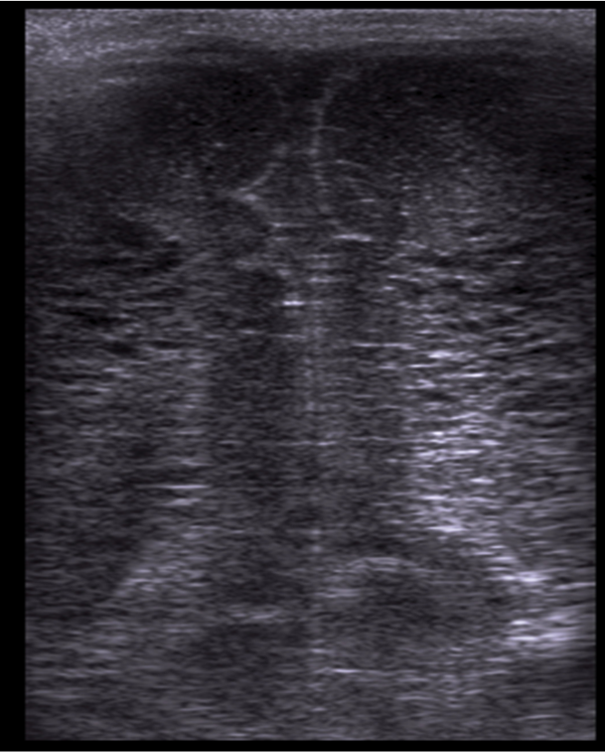

Neonatology Grade 2 PVL 1 Image